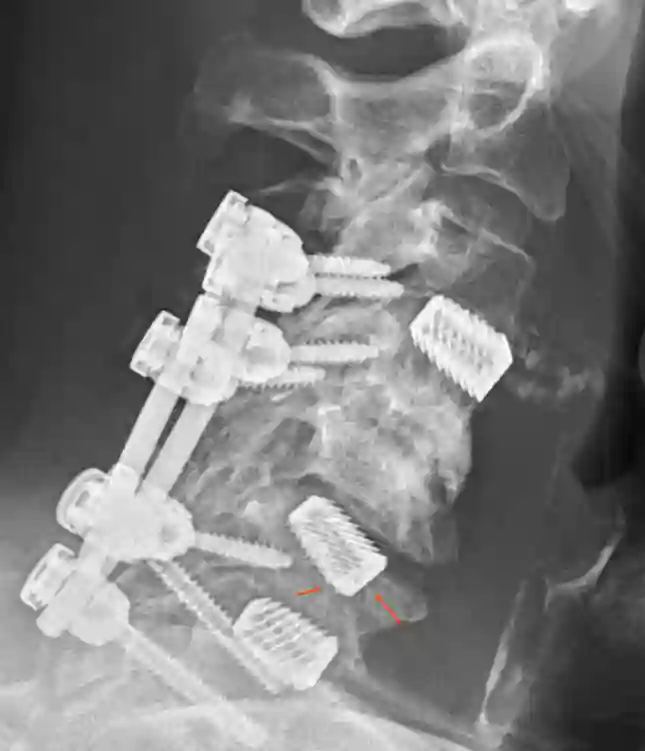

Platte

In manchen Fällen ist das zusätzliche Anbringen einer Platte sinnvoll oder auch notwendig. Beim Anbringen einer Platte sollte darauf geachtet werden, dass die Platte nicht mehr als 50 % der letzten von der Platte betroffenen Wirbelkörper abdeckt, um Anschlussosteophyten zu vermeiden[^3]

Bildgebung